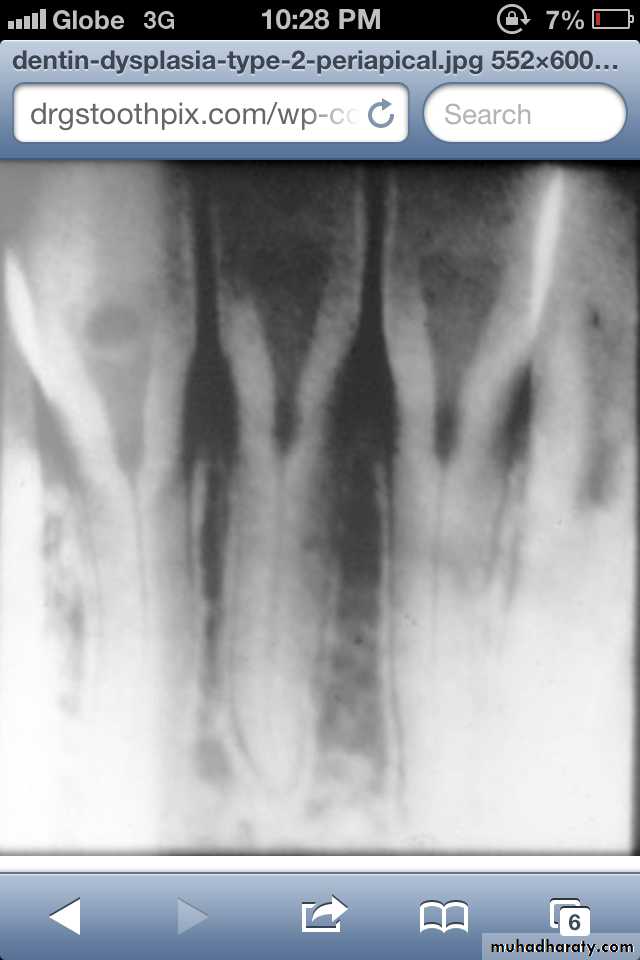

Dentin dysplasia, type II. panoramic &periapical films of the same case show obliteration of the pulp chamber, reduction in the caliber of root canals, and pulp stones obscuring the flame-shaped pulp chambers.

Periapical inflammatory lesions are associated with some of the mandibular anterior teeth.